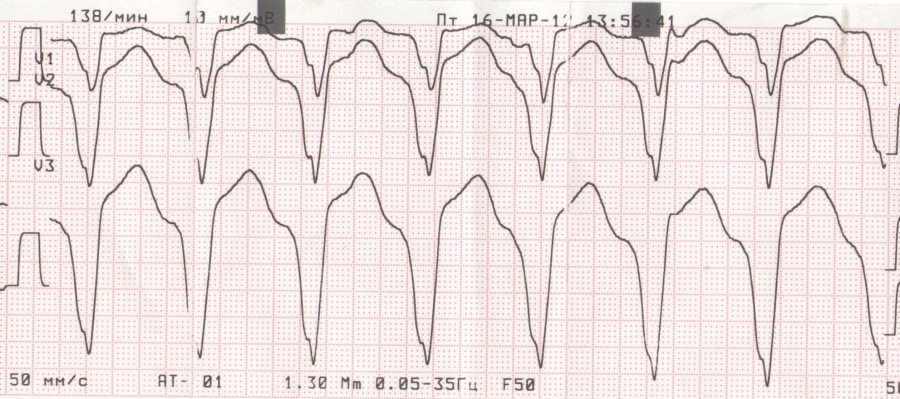

Желудочковая тахикардия. Улетевшая тема 6953.